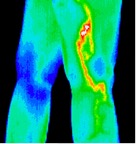

9- Phlebitis.jp2

Phlebitis

10- Varicosity in right leg.jp2

Varicosity in right leg